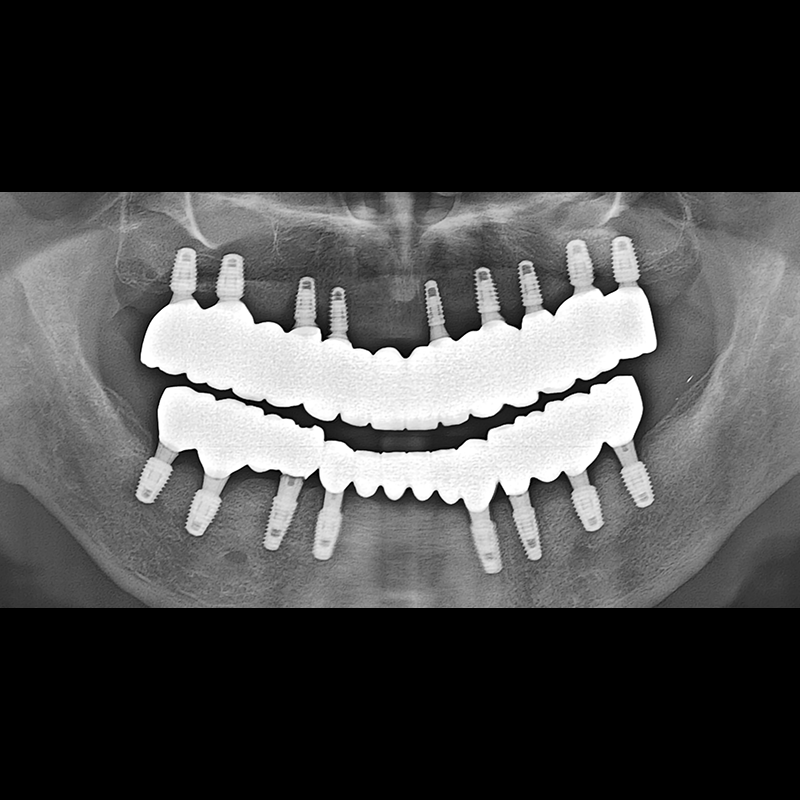

BEFORE AFTER

インプラント手術事例 2025.05.30

欠損した歯の部分と、生かしにくい歯の位置にインプラントを植立しました。